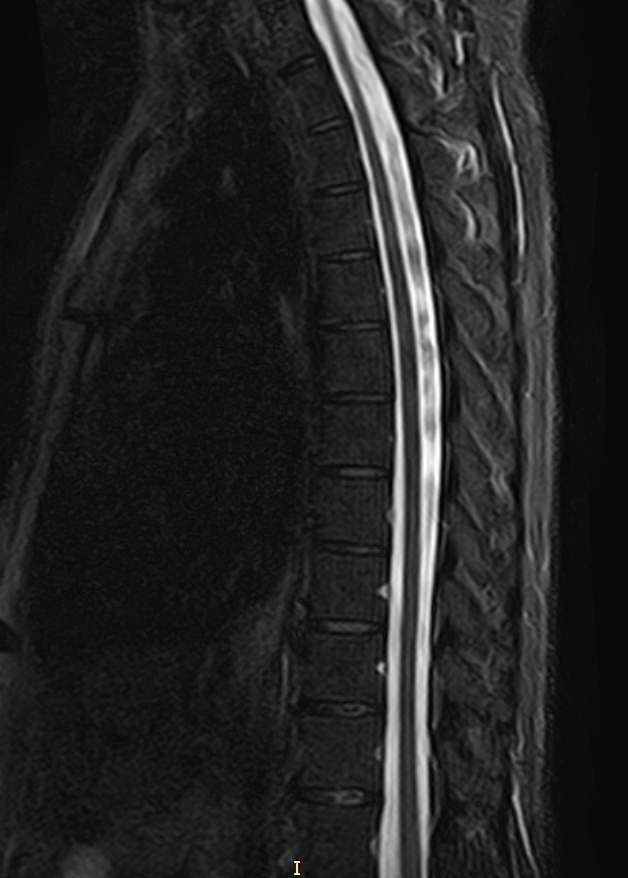

В нашей клинике мы проводим комплексное исследование, включающее МРТ головного мозга и всех отделов позвоночника. Методика комплексного обследования применяется при наличии у пациента сочетанных поражений головного мозга, спинного мозга и позвоночного столба.

Стандартная МРТ головного мозга дает важную информацию о состоянии и структуре мозговой ткани для выявления большого числа заболеваний, в том числе опухолевых образований, демиелинизирующих заболеваний, воспалительных процессов головного мозга и мозговых оболочек.

При подозрении на распространенный процесс с поражением различных уровней позвоночника целесообразно проведение МРТ для диагностики дегенеративно-дистрофических заболеваний, травматических, воспалительных изменений, а также опухолевых процессов позвоночника. Метод позволяет оценить состояние структур позвонков, позвоночного канала с расположенным в нем спинным мозгом и окружающих мягких тканей, кроме того, является основным способом диагностики демиелинизирующих заболеваний спинного мозга.

Исследование проводится на современном томографе TOSHIBA VANTAGE TITAN 1,5 Тесла. За счет высокой индукции магнитного поля аппарат обладает  высокой разрешающей способностью, что позволяет проводить точную диагностику заболеваний центральной нервной системы и позвоночника.